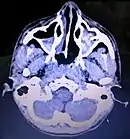

Maxillary sinus cancer that has spread to the brain